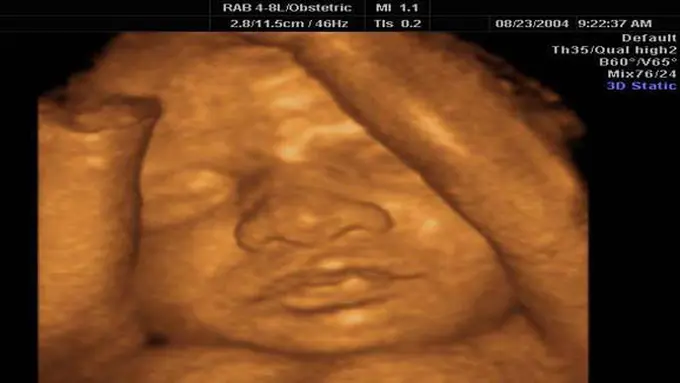

Jika pada USG 2 dimensi anda hanya dapat melihat “penampakan” janin berupa gambar dua dimensi yang berwarna hitam putih, pada USG 4 dimensi “penampakan” janin jauh lebih jelas dan tampak nyata.

Seperti dilangsir dari situs seebaby.org, USG 4 dimensi memanfaatkan teknologi 3 dimensi namun dengan movement bayi yang terlihat jelas. Jadi, melalui USG 4 dimensi, anda seperti melihat rekaman pergerakan bayi anda.

Pada USG 4 dimensi, anda bisa melihat pergerakan bayi anda dengan cukup jelas; seperti saat bayi anda berkedip, menguap, dan membuka mata. Wow, amazing sekali, kan, anda sudah bisa melihat buah hati anda bahkan sebelum dia lahir.